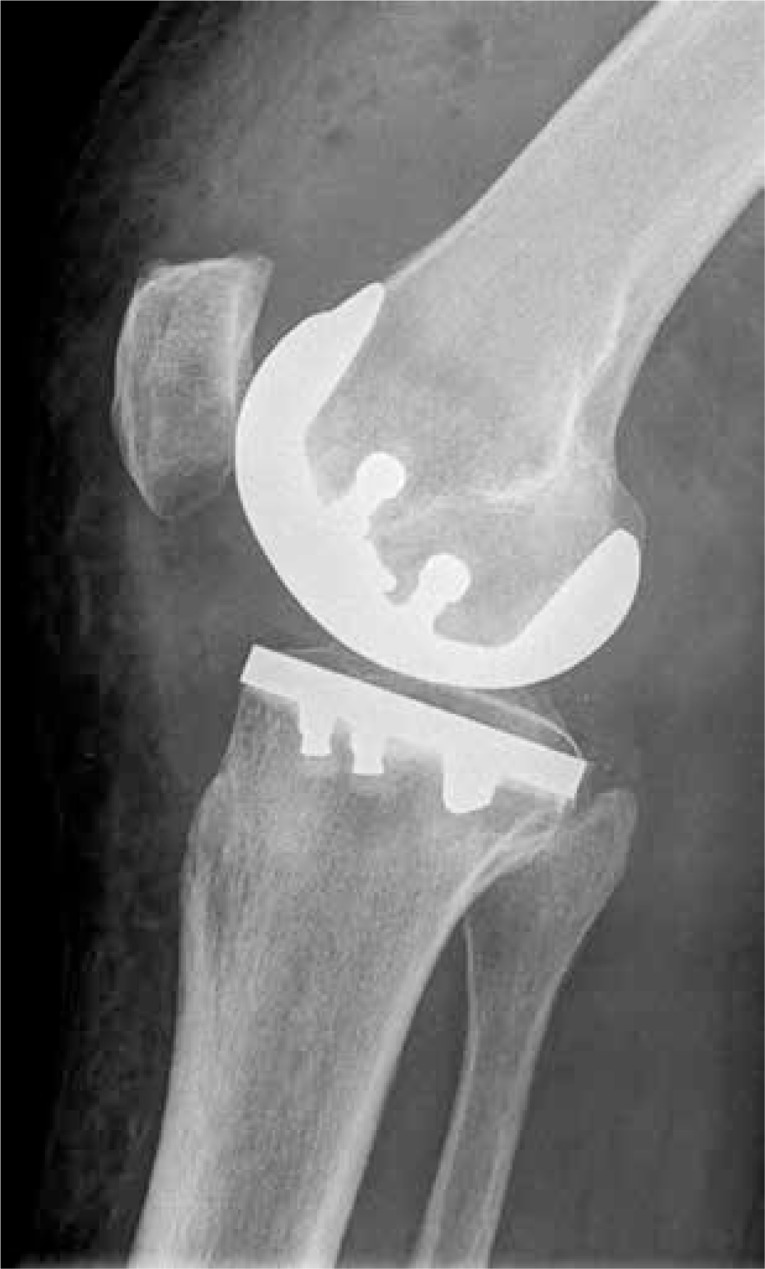

Figure 2.

Lateral postoperative radiographic view of a representative knee joint after iDuo implantation

An ideal fit of the tibial component was registered in 19 patients without any measurable overhang or underhang on AP or lateral view radiographs. A minor lateral overhang (< 2 mm) of the tibial component was recorded in 7 cases (1.01 ±0.46 mm) and a minor underhang (< 2 mm) of the tibial plateau in 4 patients (0.87 ±0.47 mm). None of the patients had an overhang/underhang of 3 mm or more in any direction. Overall, representative lateral radiographic views showed an excellent fit of the femoral and tibial components without any signs of significant overhang, underhang or femoral notching (Figure 2).

The slope of the tibial component was intended to restore the natural slope of the tibial plateau. Preoperatively, the mean tibial slope measured on lateral view X-rays was 6.38 ±2.4°, and 6.14 ±2.40° in the iView planned protocol. Postoperatively, this was consistently reproduced, resulting in a mean slope of the tibial implant of 5.77 ±1.97° upon determination on postoperative lateral view X-rays (Figure 2).

The patella height was well preserved as demonstrated by the values of the Insall-Salvati ratio. Pre-operatively the average Insall-Salvati ratio was 1.078 ±0.11, while the corresponding post-operative measurement was 1.072 ±0.11. This was also confirmed by the modified Insall-Salvati ratio, which was 1.747 ±0.28 pre- and 1.733 ±0.27 postoperatively.